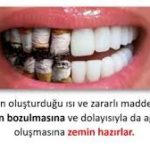

- Diş lekeleri ve renk değişimi: Nikotin ve katran dişlerde sarı veya kahverengi lekelenmelere yol açar.

- Diş çürümesi riski: Sigara tükürük akışını azaltarak ağızdaki doğal temizlenme mekanizmasını bozar, bu da çürük riskini artırır.